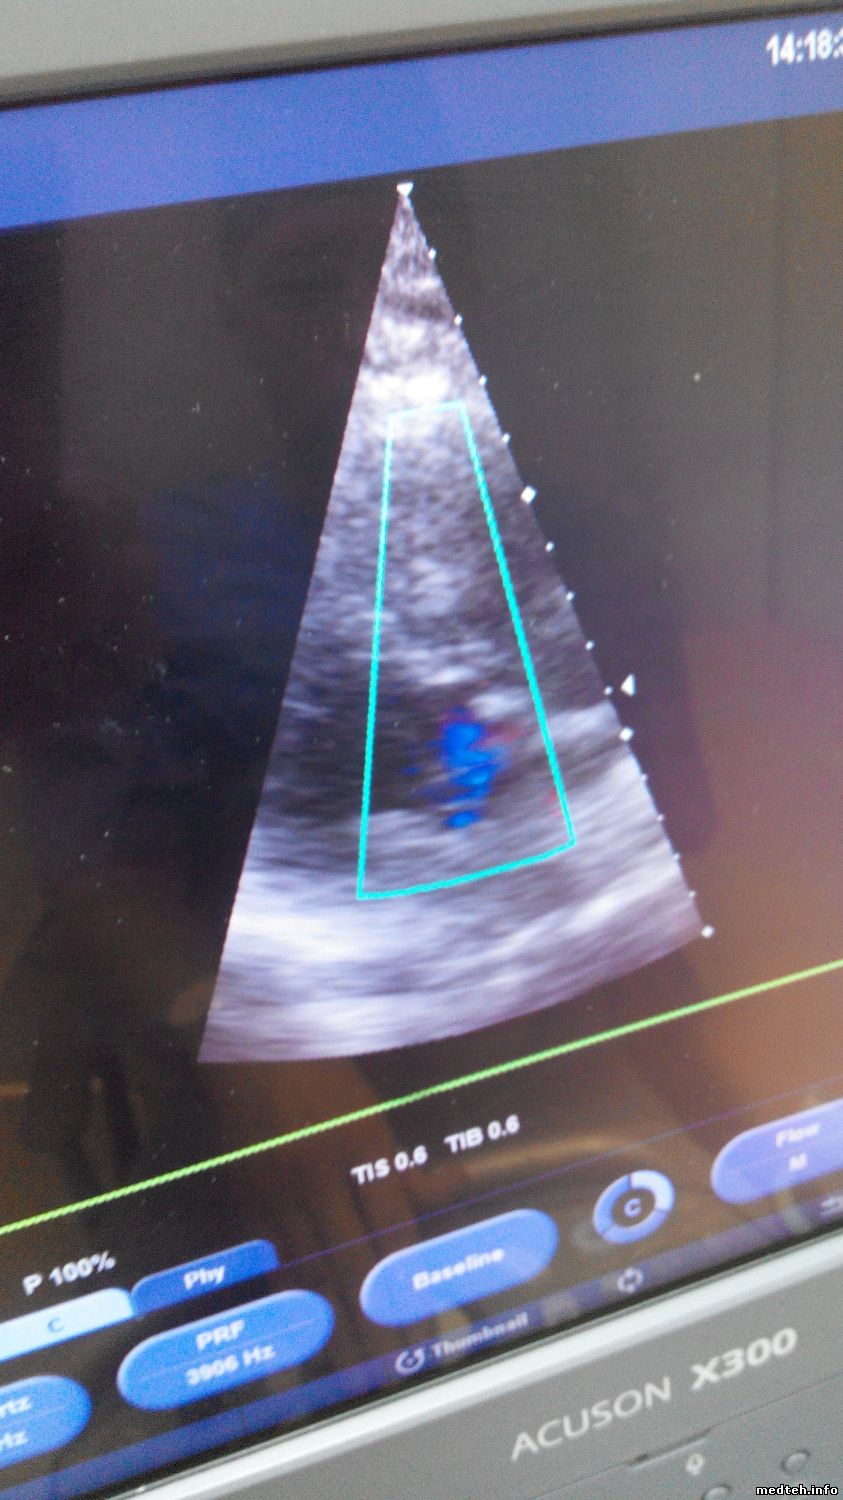

А на моём УЗИ, эти же датчики, при сердечном кровотоке ШУМЯТ!!!! ПОМЕХИ и прочую паразитивную гадость показывают!!!!!!!!!!!

Вот фото с помехами, я настроил чувствительность так, что я даже не дотрагиваюсь до них, а картинка КОШМАРНАЯ!!!!!!

А вот как ведут эти же датчики на исправном УЗИ аппарате:

Без помех- строго по делу!!!

Senergy а при чём всё это. Если судить по фото(9335664.jpg(254Kb) · 1234473.jpg(243Kb) · 2732091.jpg(266Kb) · 7290124.jpg), то у вас просто умерла плата доплера, вот она и даёт такую характерную картинку.